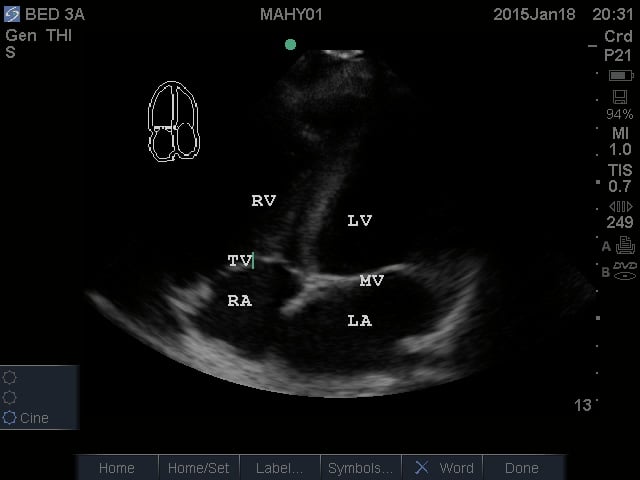

- Apical Four Chamber View: This view shows all four chambers of the heart. The apex is toward the near field with the interventricular septum pointing to approximately the 12 o’clock position. By fanning superiorly, the apical five chamber view can be obtained, with the “fifth chamber” being the LVOT with the aortic valve.

- Figure 4. Apical Four Chamber view. RV = Right ventricle. LV = Left ventricle. TV = Tricuspid valve. RA = Right atrium. LA = Left atrium. MV = Mitral valve

Video 4. Normal Apical Four Chamber View